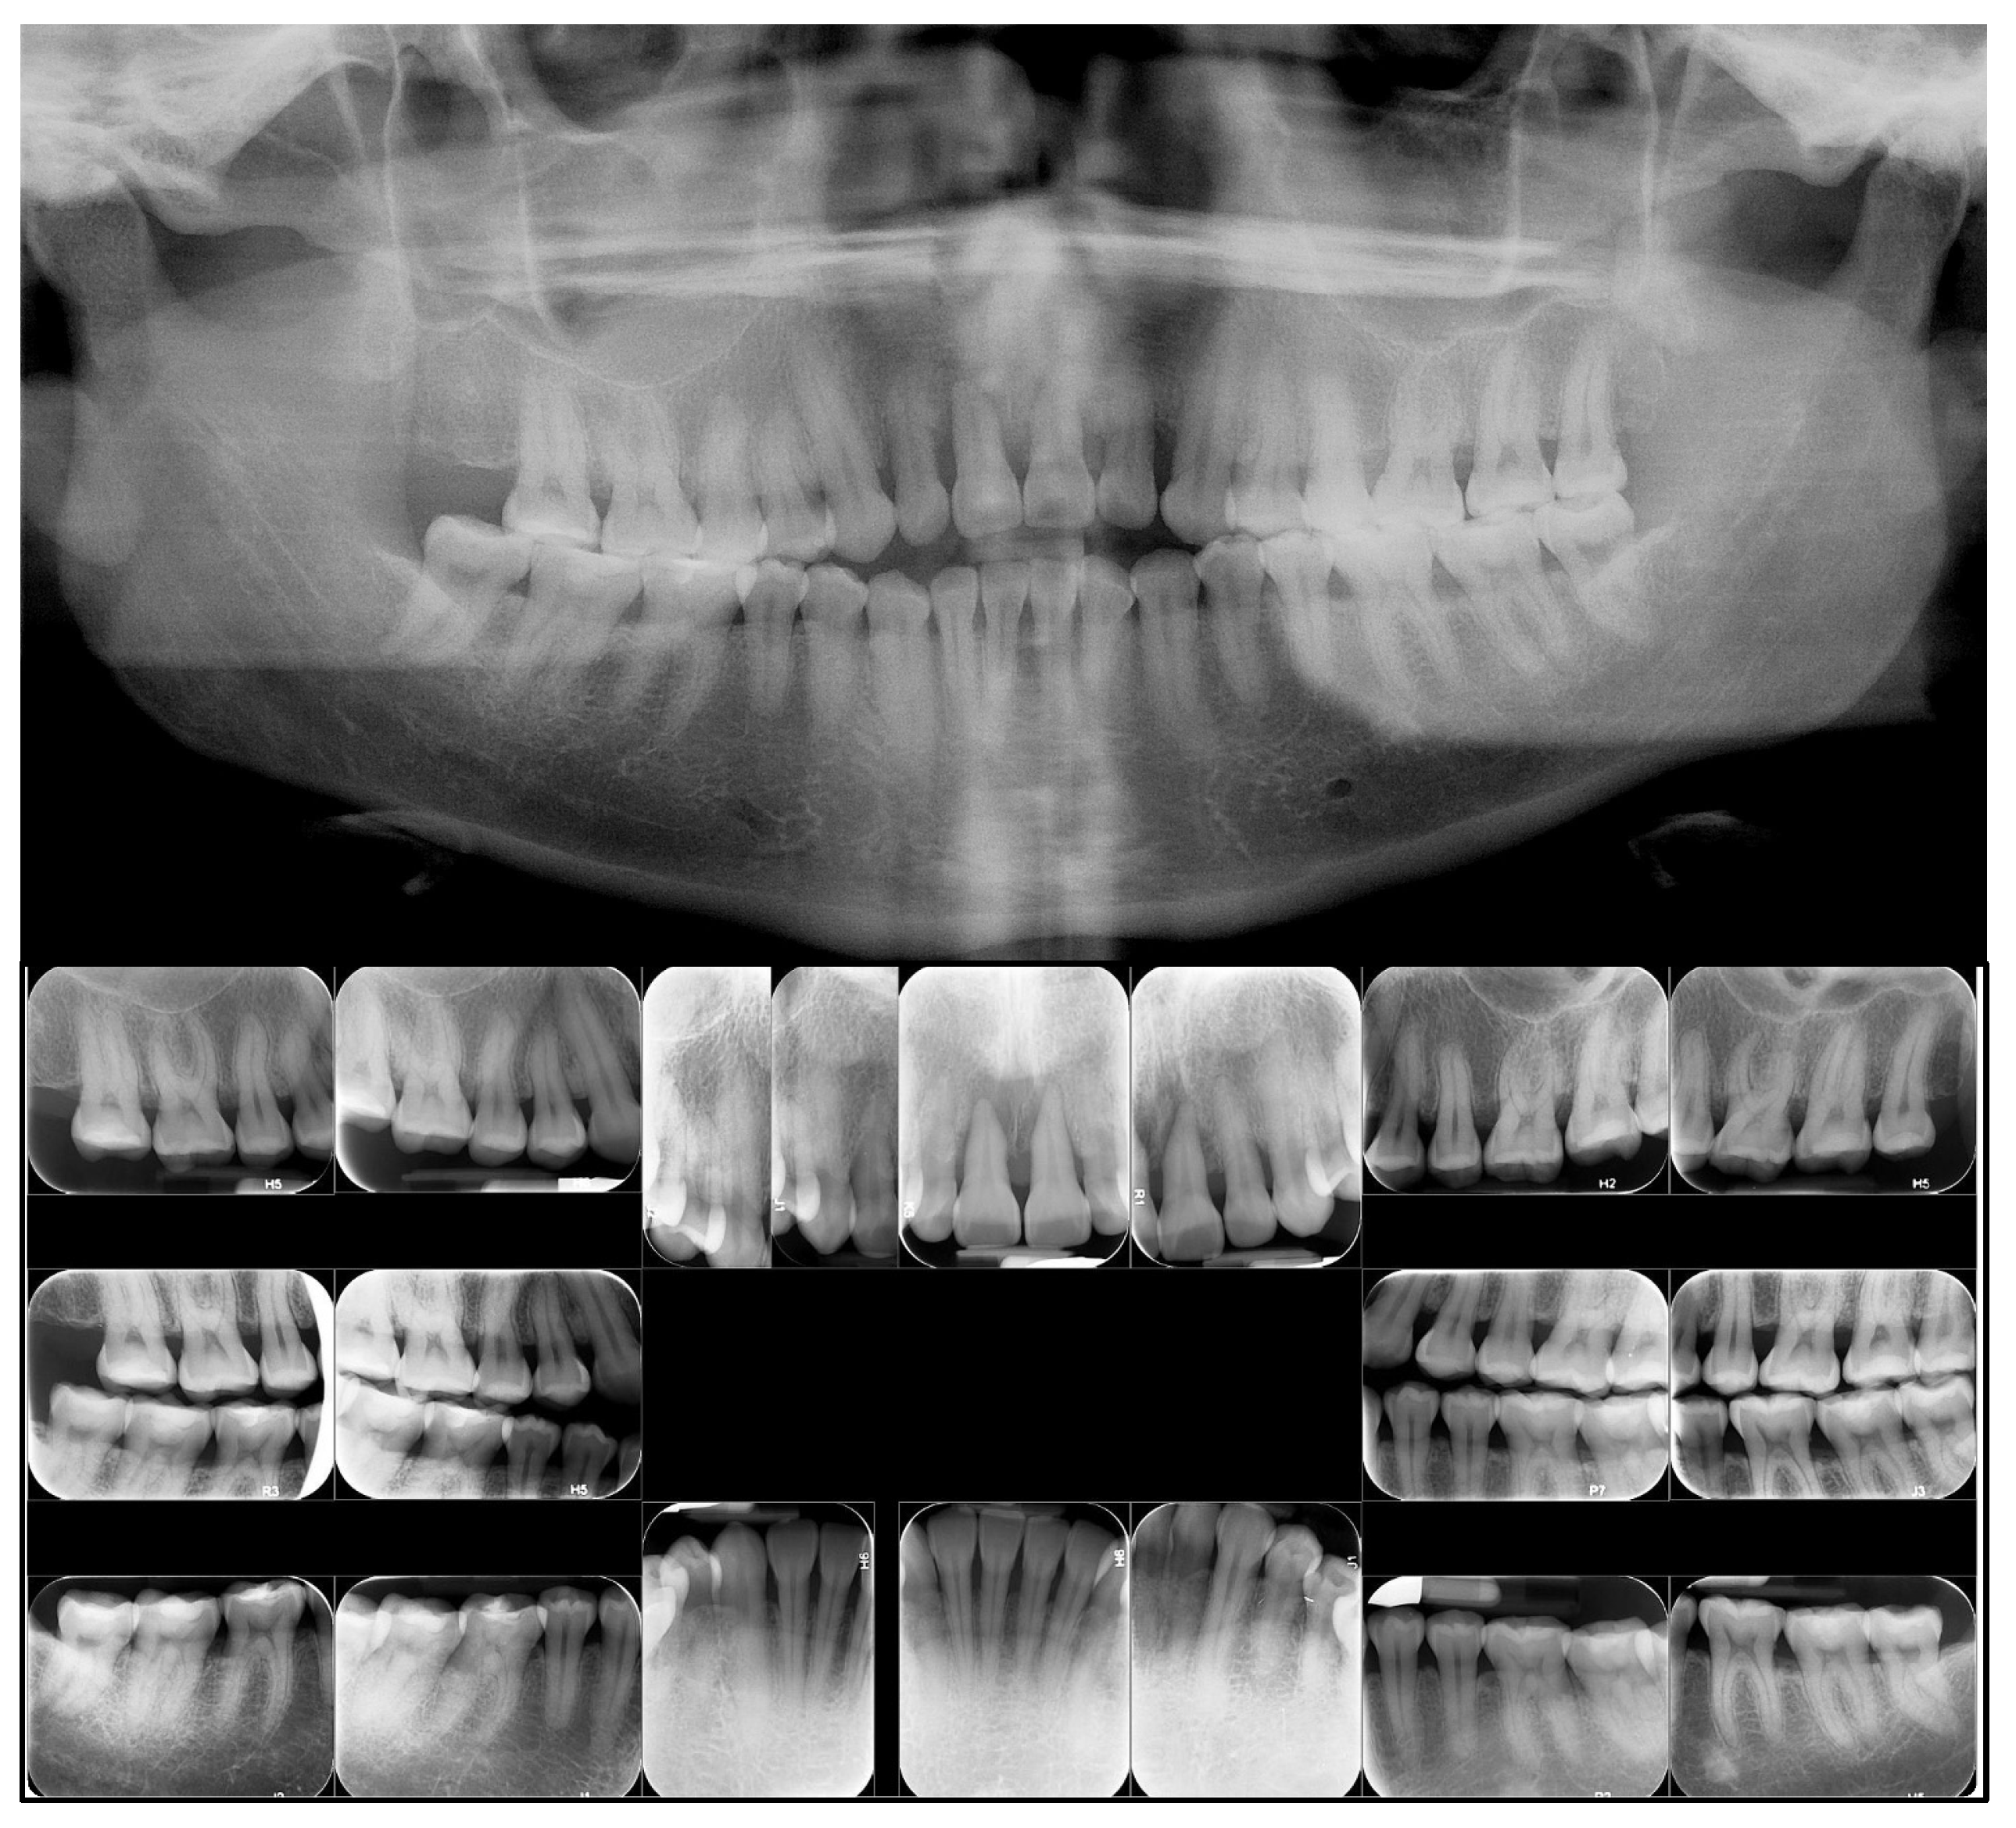

2. Case Presentation

2.1. Diagnosis and Etiology